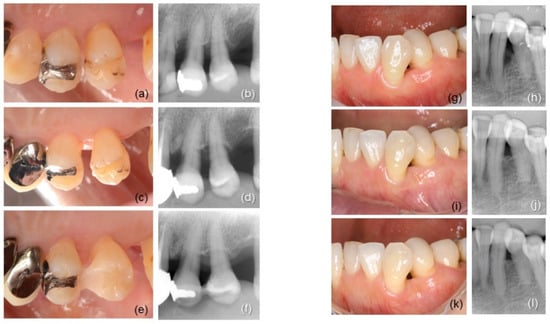

3.4. Radiographic Outcome

3.5. CAL Gain and RBF in Different Defect Configurations